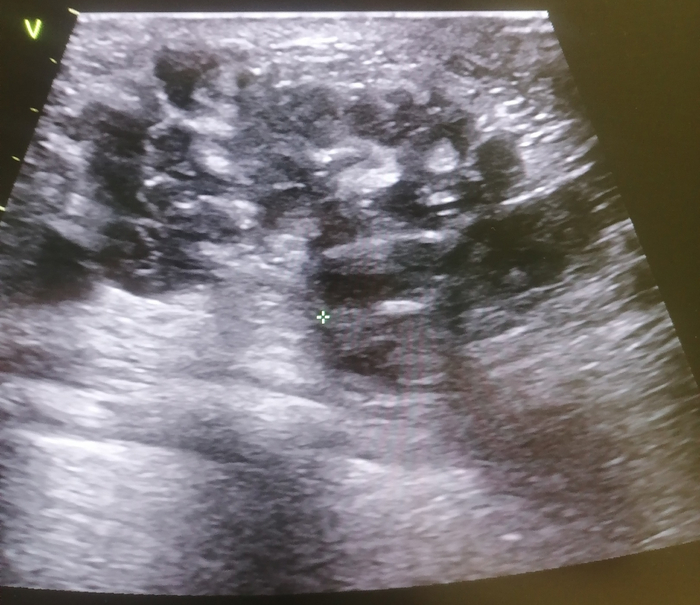

BIRADS 5 - высокий риск злокачественности. Всякие лучистые контуры, неровные, плотные образования с тенями и т.д. попадают сюда. Биопсия при выставлении такой категории практически неизбежна.

Так же между четверкой и пятеркой, ближе к пятерке